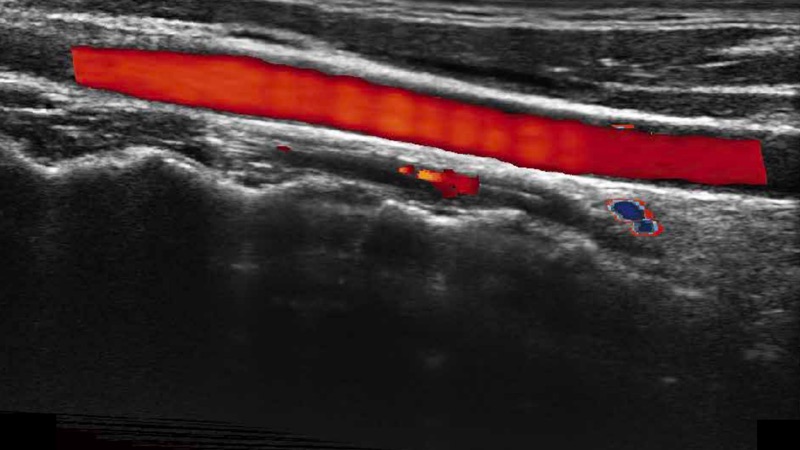

高分辨率血流成像技术提高了对低速血流信号的检测能力。在提高空间分辨率的同时,也克服了血流外溢现象,为用户提供更加真实的血流动力学信息。

通过色彩血流和实时宽景相结合,可观察到完整的静脉或动脉的血流,方便医生检查。实时扫查过程中,如有任何操作失误也可以很容易地进行回扫擦除,而不会中断扫查。